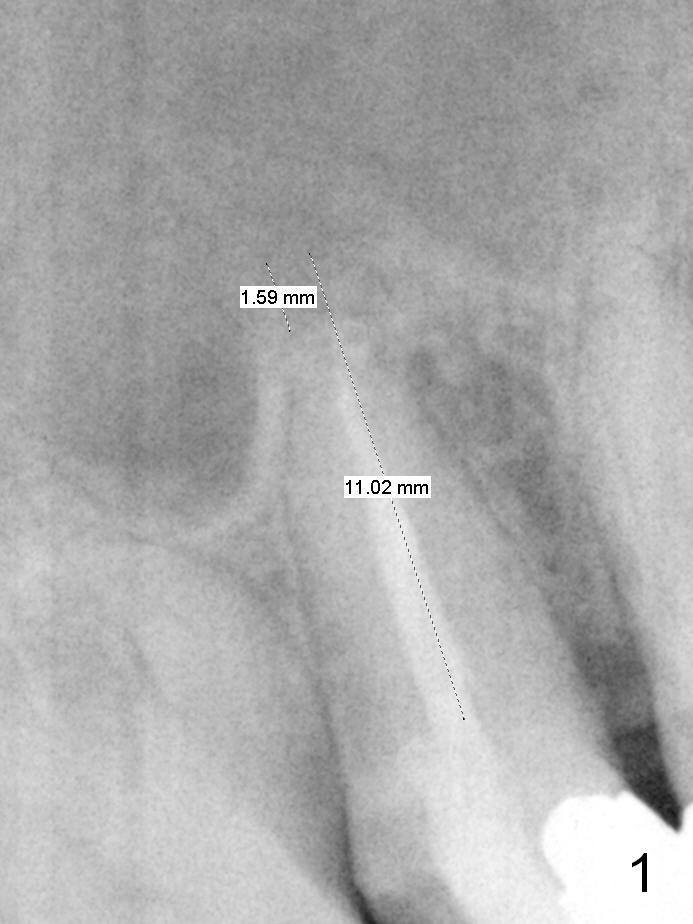

To prevent sinus lift related sinusitis, a shorter implant is going to be placed (Fig.1), approxi-mately 2 mm beyond the apex. Following extraction, the buccal plate (Fig.3a (coronal section): B) is not only ~ 2 mm shorter than the palatal one (P), but also thinner. Since the bone density of the palatal plate is higher, without osteotomy an implant is less likely placed in the middle of the socket (S (Fig.1); Fig.3b) than buccal (Fig.3c). Therefore drills are used to form osteotomy in the apical 1/3 of the palatal slope (Fig.3d (red arrow); SM: sinus membrane). When 3.3 mm Magic Drill (MD) is in place (Fig.2), the distal surface of the sinus septum is perforated without air leakage. Demineralized allograft (.0125-.085) is placed for sinus lift (Fig.4 *) prior to placement of 4.5x11 mm implant with ~ 30 Ncm. The implant is slightly buccal to the ideal position indicated in Fig.3e (curved blue line: sinus lift). A 4.5x4(2) mm pair abutment is placed for an immediate provisional to hold mineralized allograft in the remaining socket gaps (Fig.4 arrowheads, .5-1.5 mm). A 9 mm implant may avoid sinus floor perforation on the distal slope of the 2nd premolar. The osteotomy should have been established initially as mesial as possible. In fact the patient has nasal hemorrhage while sneezing for the first 2 days postop. Although he complains of pain buccal to the implant, the gingiva appears to heal 7 days postop (Fig.5). The distobuccal papilla appears to be displaced somewhat. Raising mucoperiosteal flap is most likely associated with postop pain and esthetic compromise. The implant appears to have osteointegrated 5 months postop (Fig.6). A 4.5 mmx15° 3 mm cuff angled abutment is placed for final restoration. The distolingual portion of the implant is supported by the regenerated bone 3 years post cementation (Fig.7,8).